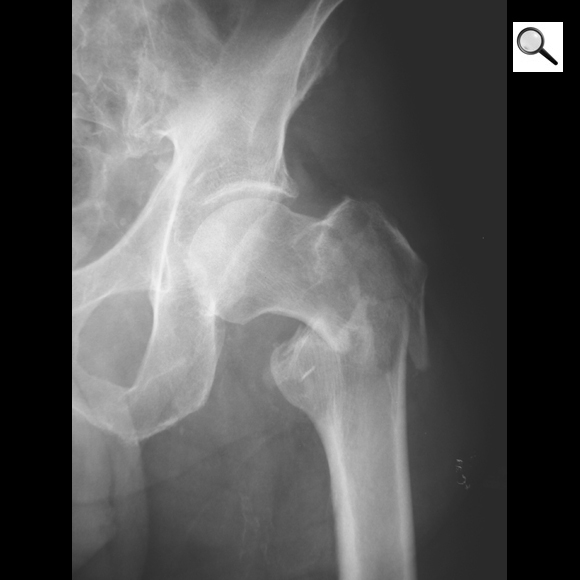

Quel est le stade Garden de cette fracture de l’ES du fémur? Quel est le risque évolutif principal?

Fracture ES fémur garden 4 car perte de contact entre fragments,

les travées osseuses sont normales

Risque max d’ostéonécrose aseptique